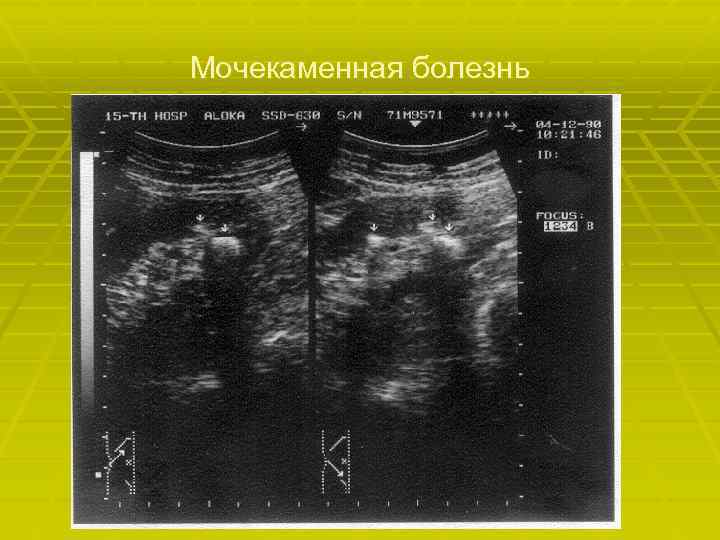

Мочекаменная болезнь